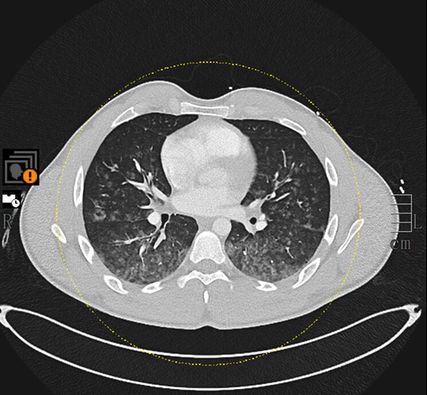

Mittels Pulmonalisangiografie-CT konnte eine Lungenembolie ausgeschlossen werden, dafür zeigten sich diffuse und ubiquitär verteilte alveoläre Konsolidierungen (Abb. 1). Eine ältere Bildgebung zum Vergleich lag nicht vor. In Anbetracht der bildmorphologischen Veränderungen wurde unter anderem die Verdachtsdiagnose einer Vaskulitis gestellt.